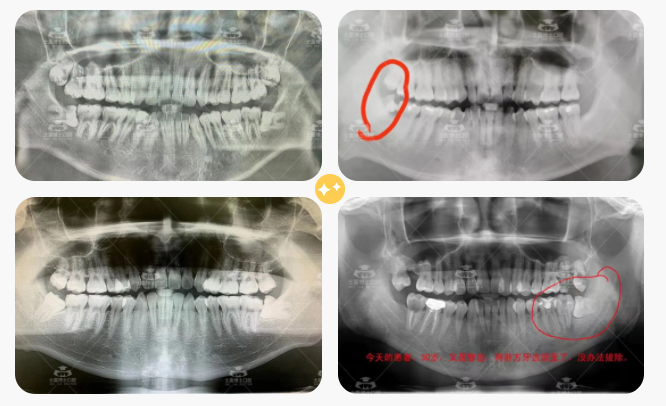

先来欣赏士嘉博士口腔医院患者口腔全景X片:

震惊!

大家看着X片里那些还没来得及拔掉的智齿,有没有人会觉得简直「负债累累」!